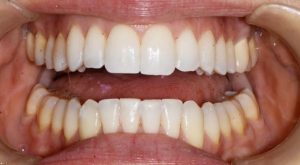

ניתוח האורתו-כירורגי הינו מיקום מחדש של הלסתות מצד אחד ושל השיניים מצד שני תוך יצירת יחס נכון יותר, הן תפקודי והן אסתטי בין הלסת העליונה והתחתונה, דבר שיאפשר מיקום נכון של השיניים במנשך תקין.